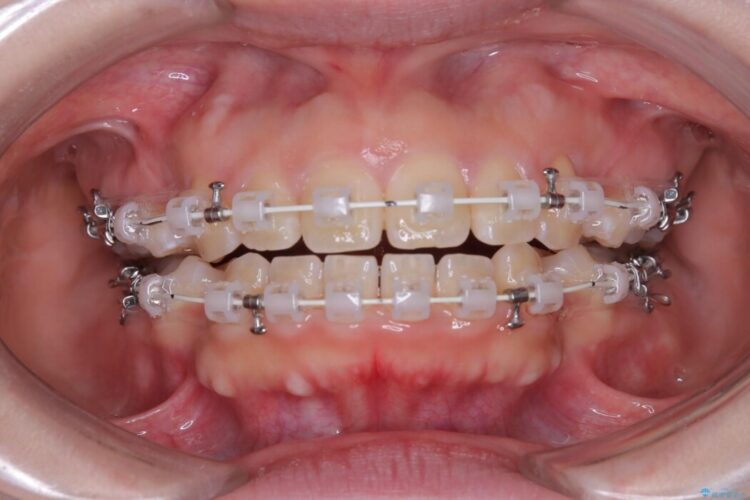

- 矯正装置:ワイヤー(審美装置)

この傾斜を根本から正し、前歯を十分に後方へ下げるスペースを確保するため、上下左右の4番を抜歯し、目立ちにくい審美ワイヤー装置にて治療を行うこととしました。

抜歯で得たスペースを活用し、大きく傾いた前歯の角度を修正しながら、ゆっくりと後方へ移動させていきました。

抜歯スペースが閉じるにつれて、唇側の圧迫感が解消され、口元のボリュームが自然に抑えられていきました。